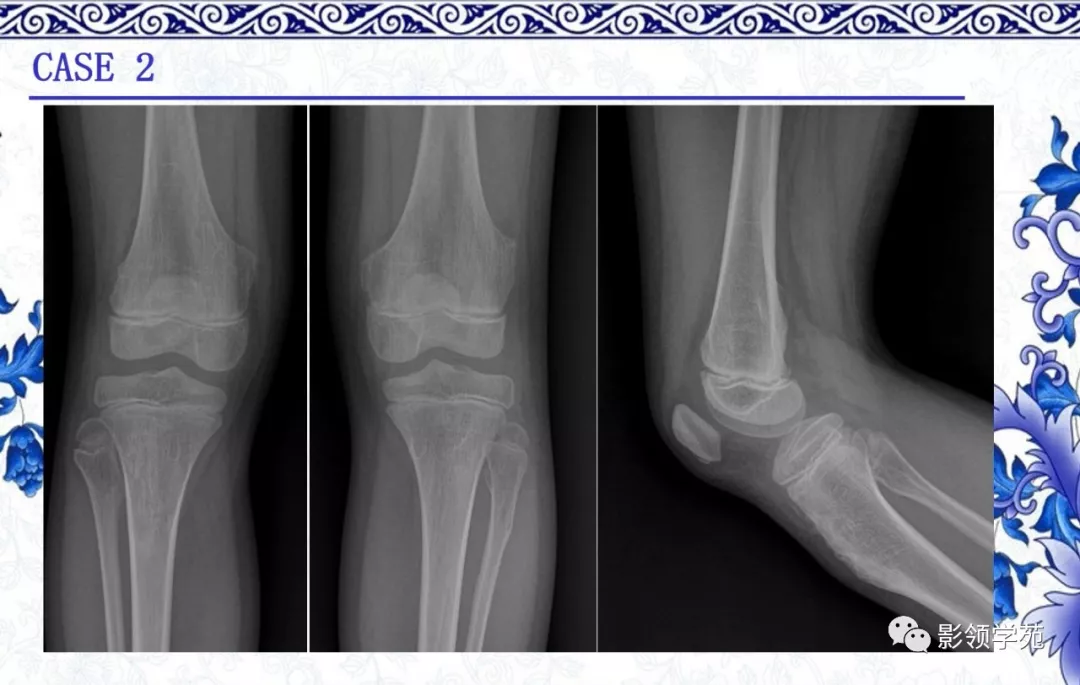

中间型——

1.软骨母细胞瘤

2.软骨黏液样纤维瘤

3.非典型软骨样肿瘤/I级软骨肉瘤